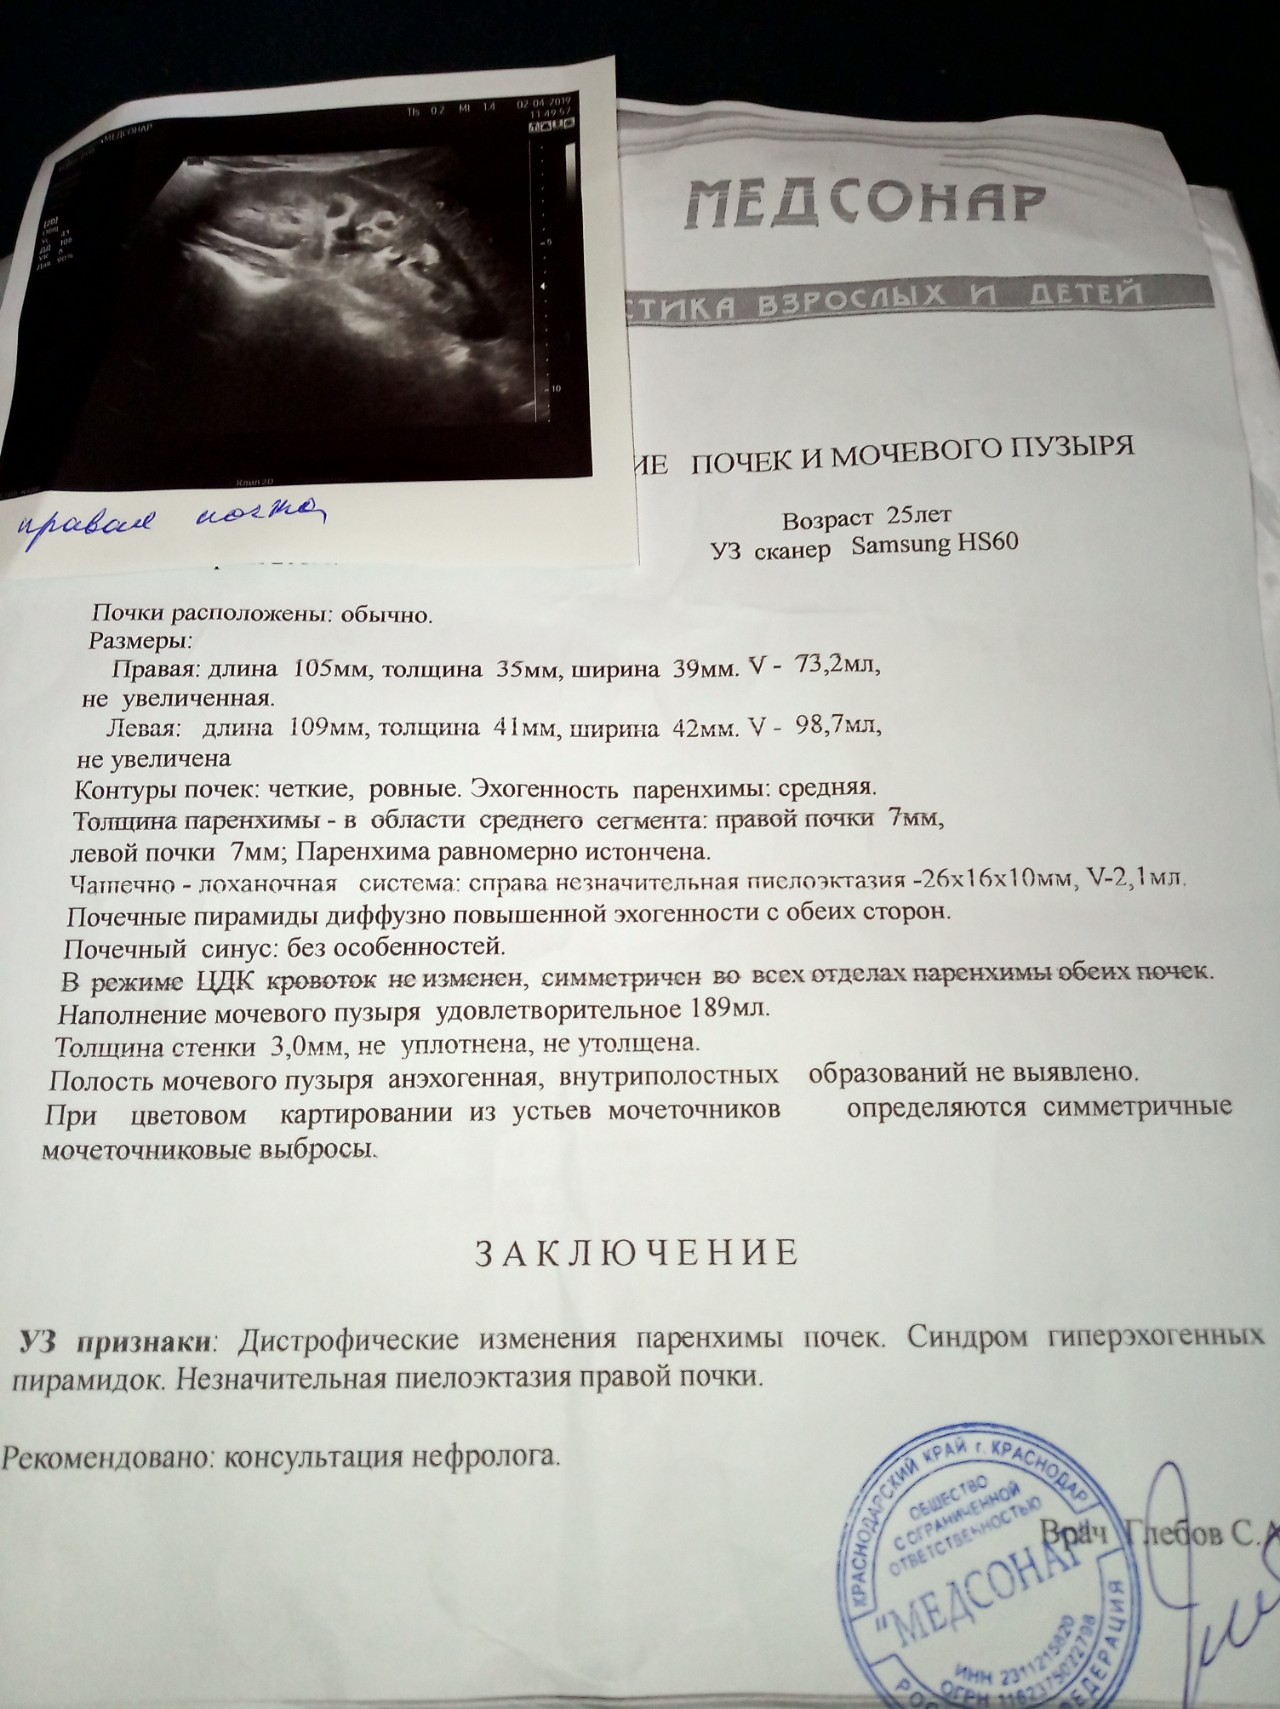

Изображения КТ конкрементов мочевого пузыря

Раздел: Идеи и советы